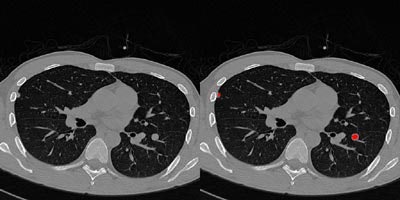

![]() |

| Above right, a pleural nodule in the right lung and a juxtavascular nodule in the left lung are accurately detected by the 3-D CAD program. No false-negative or false-positive nodules were observed in this case. Images courtesy of Dr. K. Ty Bae. |

"Our 3-D based CAD program can detect nodules including small, pleural and juxtavascular nodules in CT images with high sensitivity and a low false-positive rate," Bae concluded.